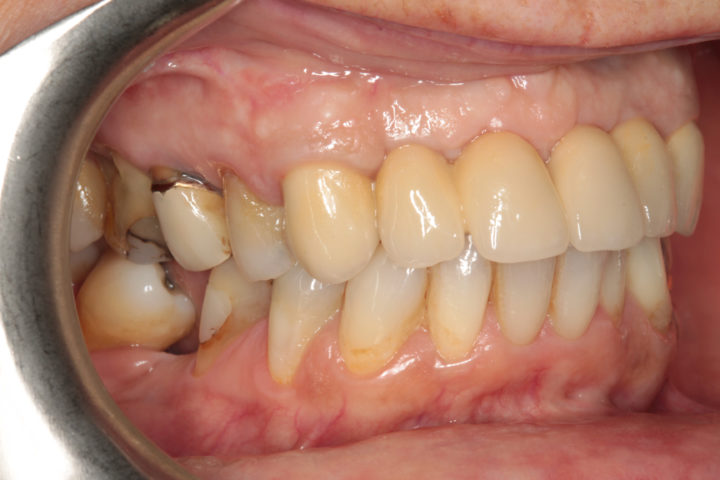

Riabilitazione di un vecchio ponte

Rimozione del ponte esistente con monconi cariati, esecuzione di estrazioni dentarie mirate, rigenerazione ossea guidata, e completamento del trattamento con un ponte in ceramica supportato da impianti in titanio.